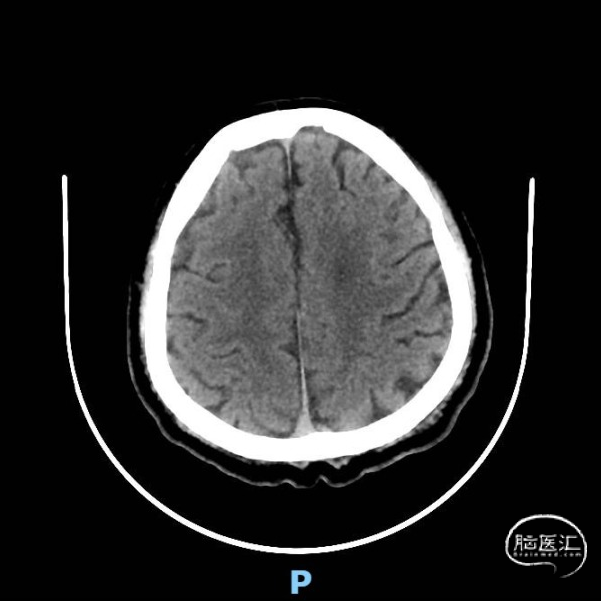

术前颅脑CT示:右侧脑室旁陈旧性腔梗。